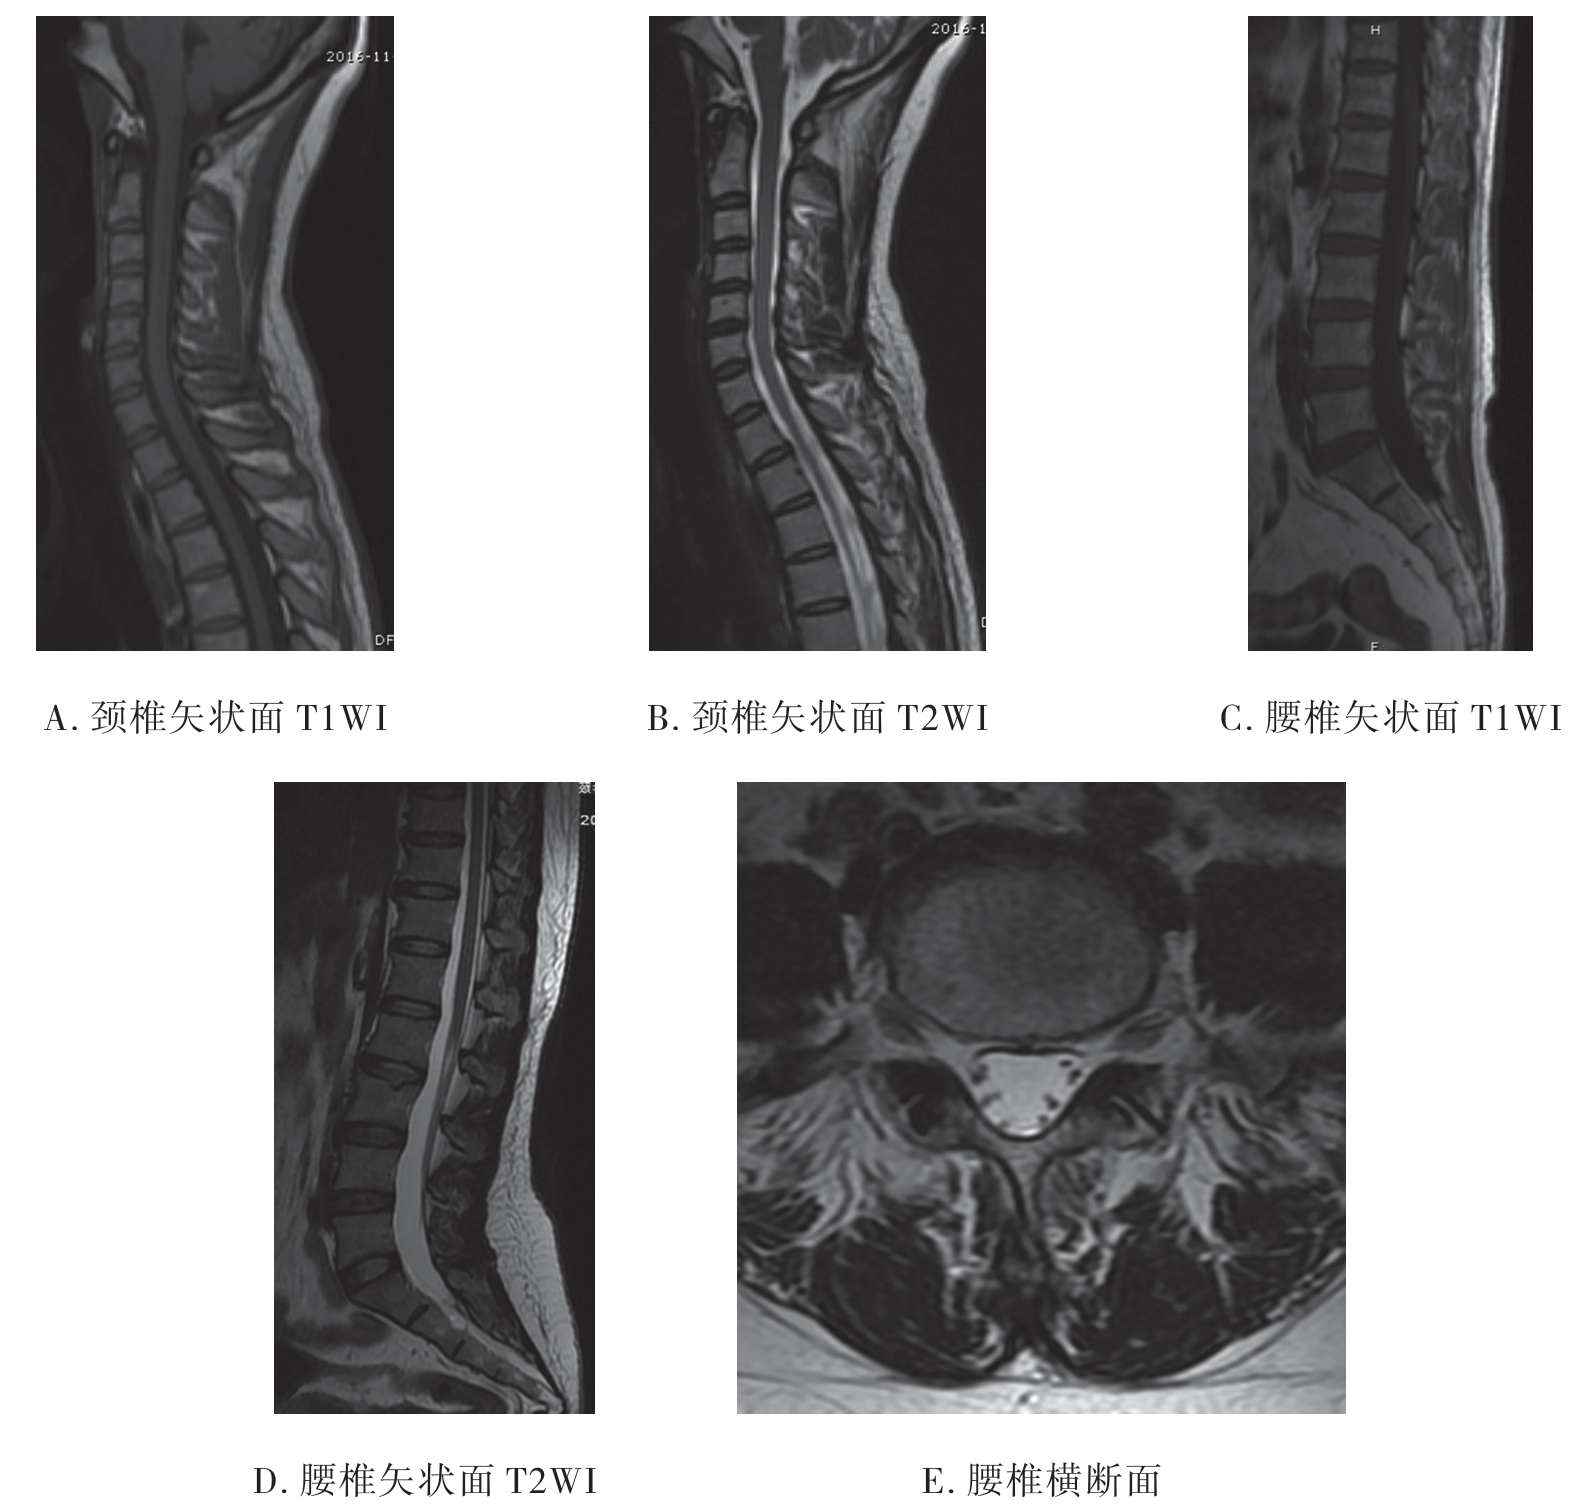

3.脊柱MRI影像 脊椎骨性结构的皮质骨及韧带在T1WI和T2WI上均表现为黑影的低信号;椎间盘在T1WI上不能区分纤维环和髓核,在T2WI上纤维环表现为黑影的低信号,而髓核则为白影的高信号;正中矢状面T1WI上脊髓呈带状灰影的中等信号,边缘光滑、信号均匀,位于椎管中心部位,其前后为低信号的脑脊液;T2WI上脊髓仍为中等信号,其前后的脑脊液呈白影的高信号。横断面上可清楚显示脊髓、脊神经及其与周围的关系(图7-2-8)。

图7-2-8 正常脊椎MRI影像